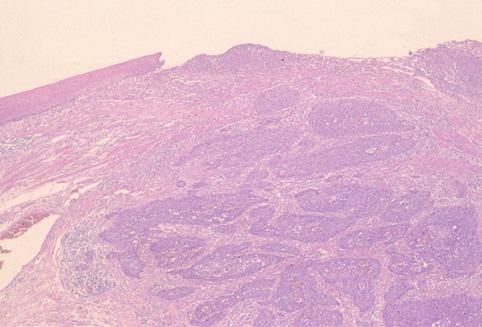

疾病(病理主体)的分类恶性上皮肿瘤/扁平上皮癌

部位(按器官分)食道/中

检查方法病理切片(微观)

肿瘤的肉眼分类0型(表在型)/IIa型(IIa+IIc)

肿瘤最大直径15~19

肿瘤的深度sm